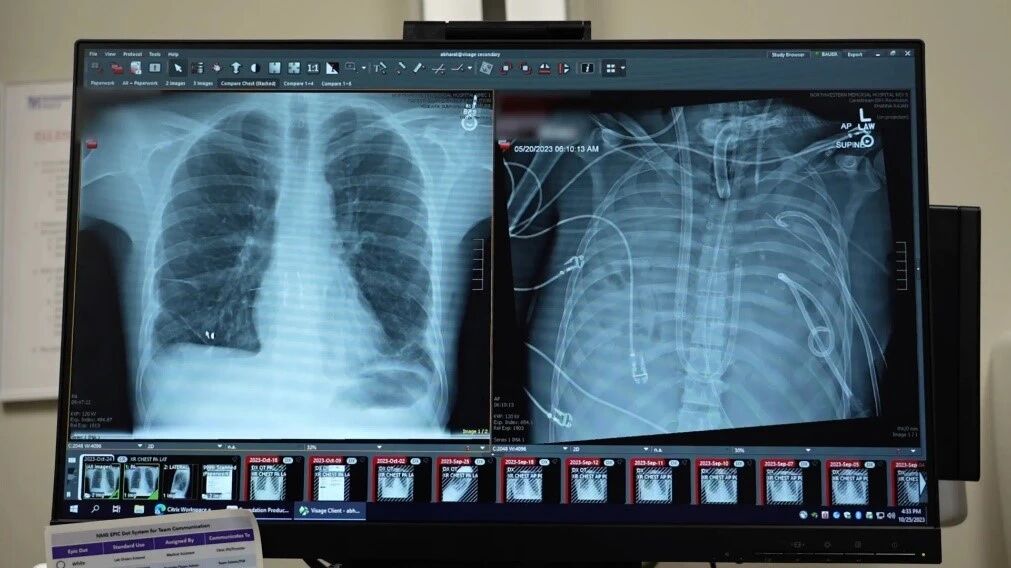

患者的新肺(左)与被切除的病肺(右)